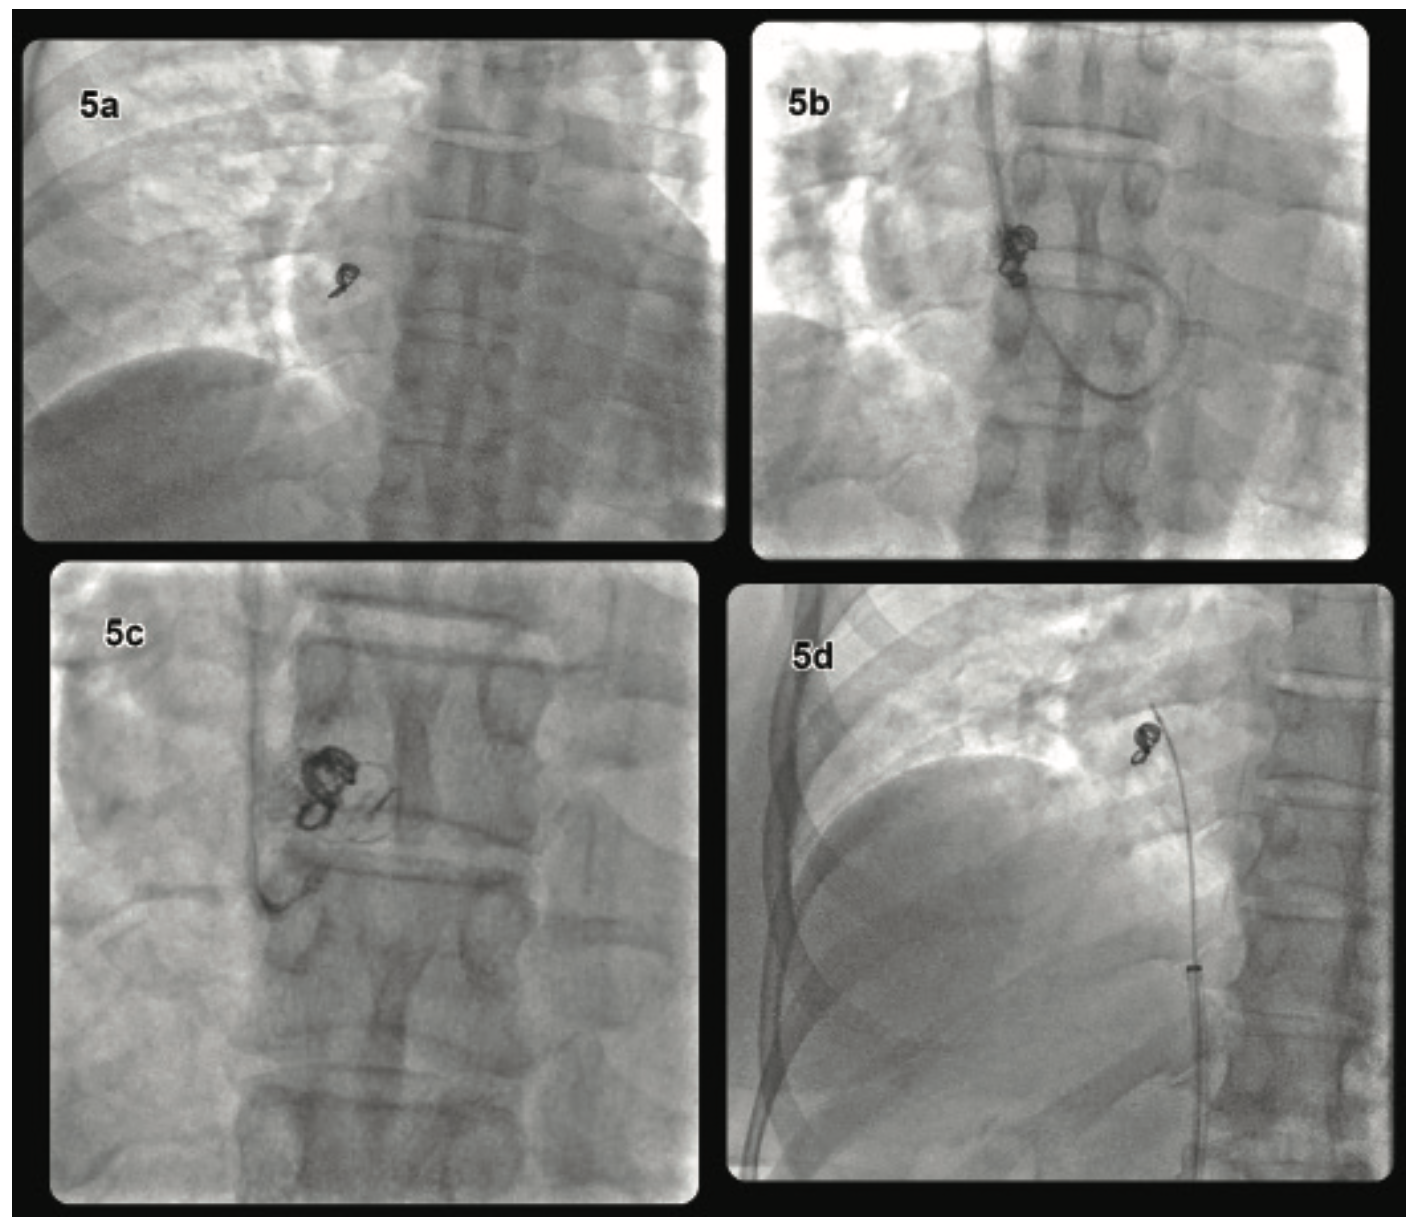

Coil Embolization for Complications Following PCI JIC Coil Embolization En Espanol This procedure is also called. se utiliza para la embolización arterial y venosa en la vasculatura periférica. Es un procedimiento para tratar vasos sanguíneos anormales en el cerebro y otras partes del. embolization is a minimally invasive procedure in which a doctor uses coils, glue, chemical agents or very small particles. healthcare providers use endovascular coiling to. Coil Embolization En Espanol.

Coil Embolization for Complications Following PCI JIC Coil Embolization En Espanol se utiliza para la embolización arterial y venosa en la vasculatura periférica. Fibras sintéticas que ayudan a la formación de los coágulos. healthcare providers use endovascular coiling to block blood flow into an aneurysm. embolization is a minimally invasive procedure in which a doctor uses coils, glue, chemical agents or very small particles. La angiografía de comprobación. Coil Embolization En Espanol.